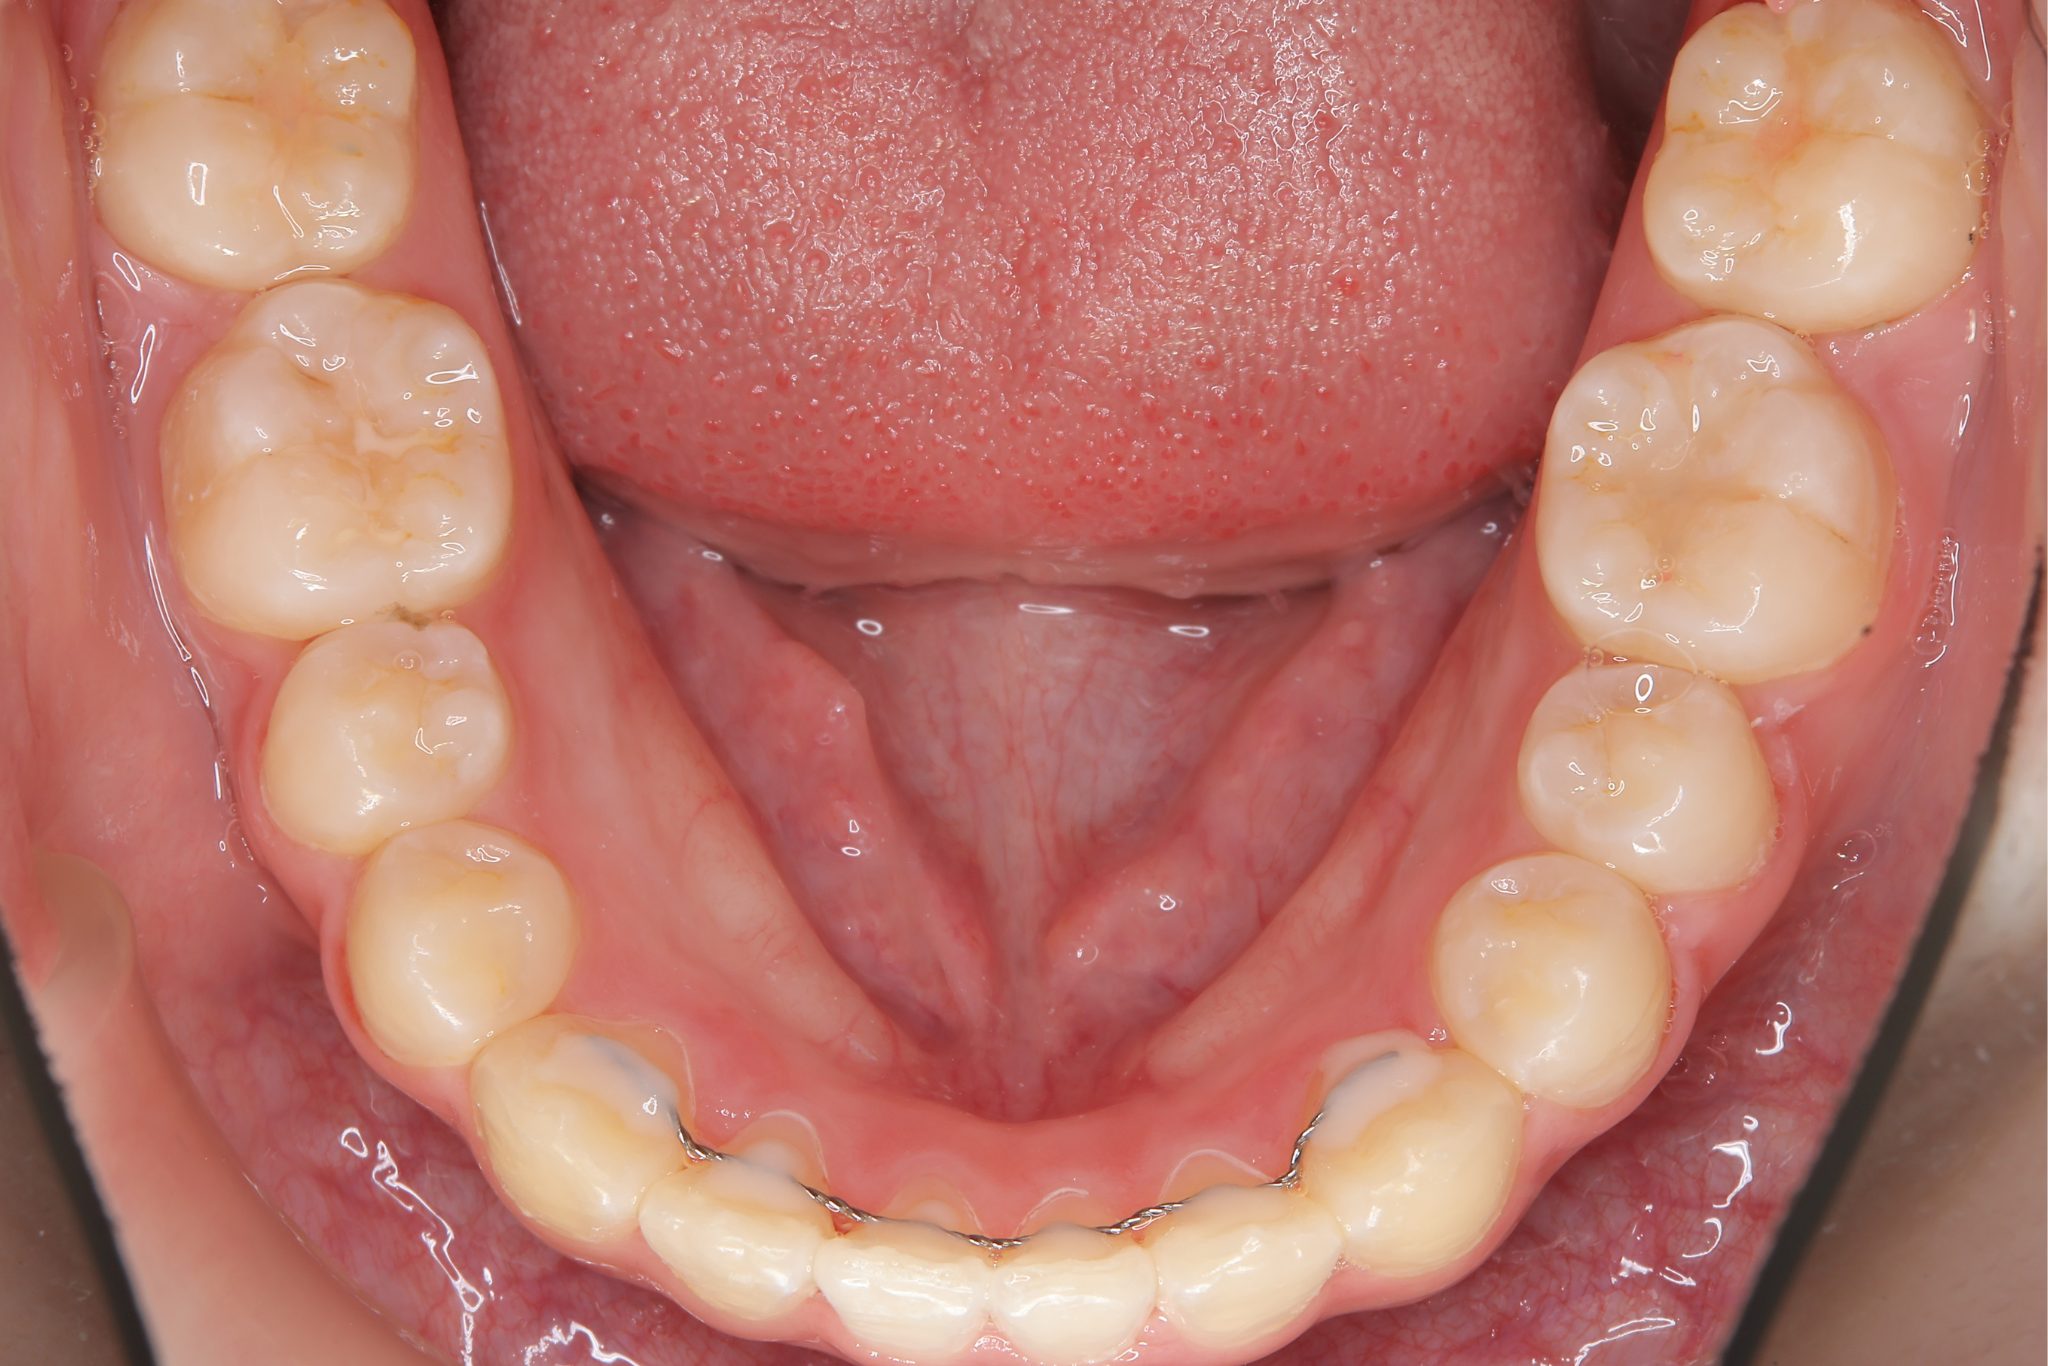

ビフォー

全顎ワイヤー矯正 症例_805

アフター

主訴 中心から前歯がずれている

施術内容 成人矯正1期治療

治癒期間 1年3か月間

費用 954,800円(税込)